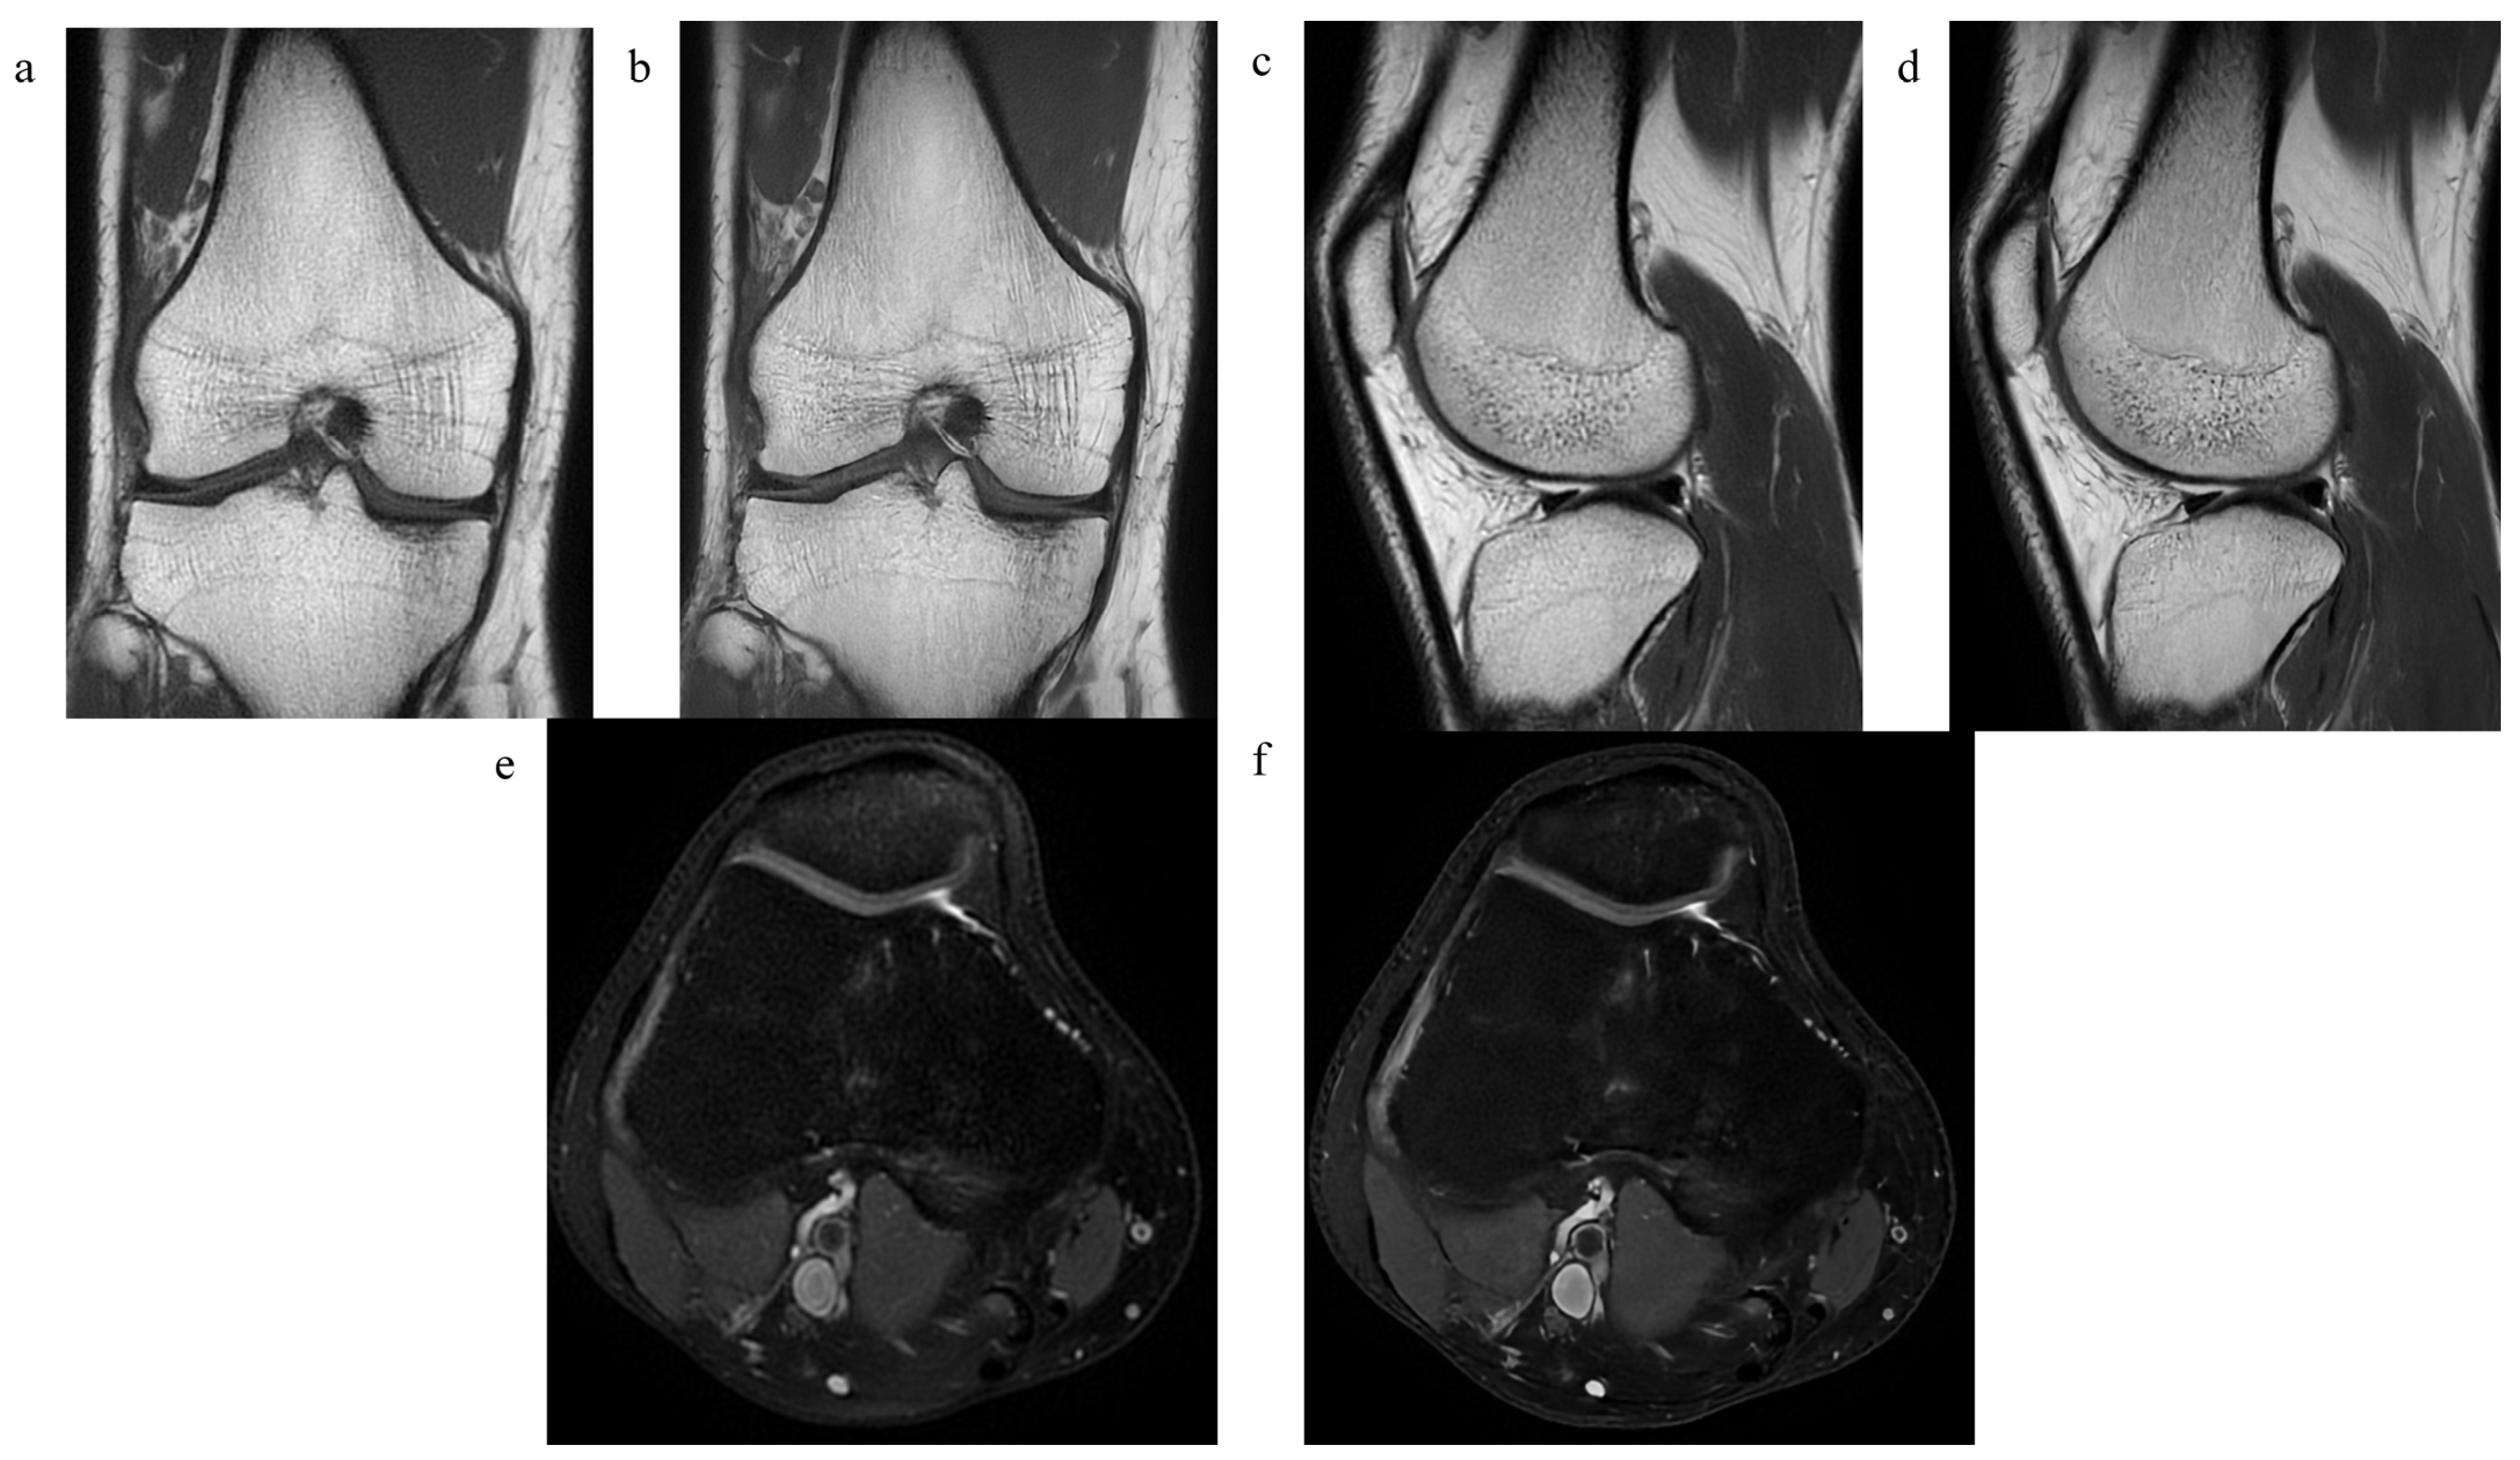

2.2. MRI Examination

3.1. The Quality of the Images and the Level of Diagnostic Confidence